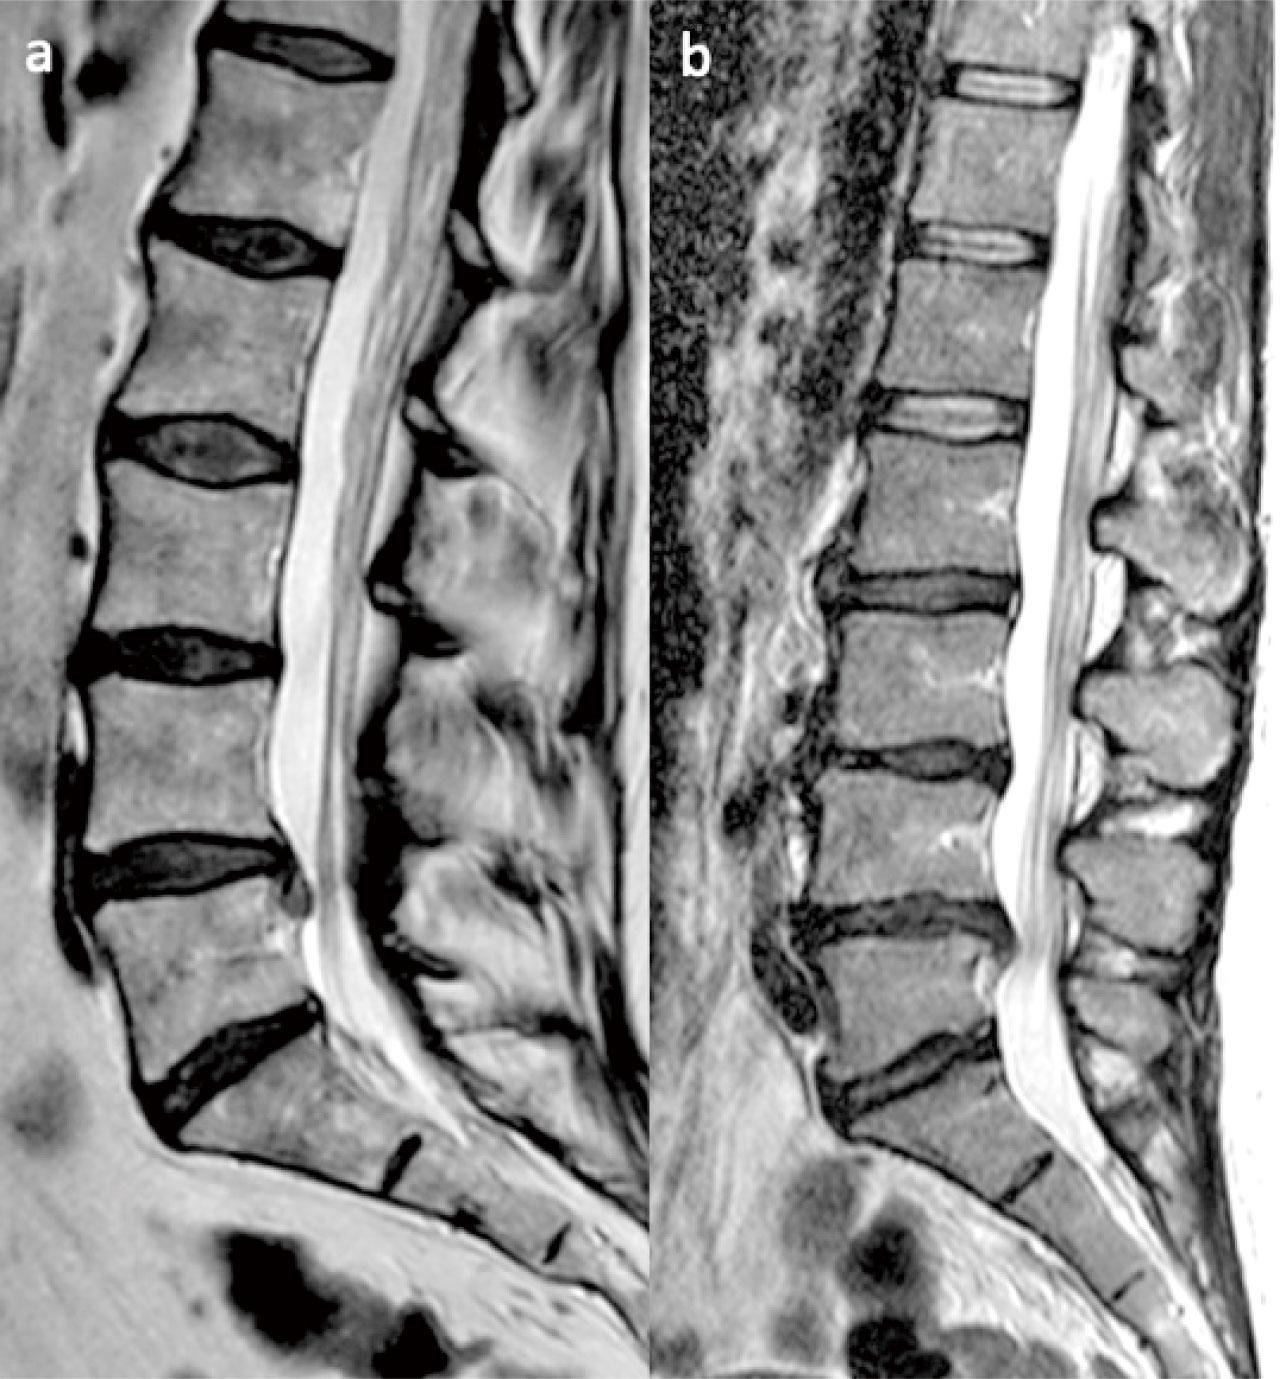

MRI(Magnetic Resonance Imaging)是繼X光後另一重要技術。由於人體不同組織中運動質子的密度不同,可以利用磁力共振的原理,在外磁場中對人體發射無線脈衝,使質子發生共振現象。MRI對軟組織的分辨率非常高,而且能從多個角度對檢查部位成像,因此在清晰度和靈敏度上都優於CT,對人體亦無害。通過對脊柱不同層面的矢狀面和所累及椎間盤的橫斷面影像,可以清晰觀察病變椎間盤突出的部位、程度、形態,以及與硬膜囊、神經根等周圍組織的關係。

腰椎間盤突出症患者由於髓核脫水退變,使其磁力共振訊號減弱。在矢狀位片中,髓核的大小、形態及訊號強弱均可以清楚反映。在正常情況下,髓核的後緣應不超過相應的核體邊緣,其訊號強度均勻。當椎間盤的退變程度愈嚴重,在矢狀位上可以看到髓核訊號進一步降低,椎間隙變窄,椎間盤向後突出超出椎體後緣,可以看到脊柱後方的神經根鞘脂肪白線受壓中斷。